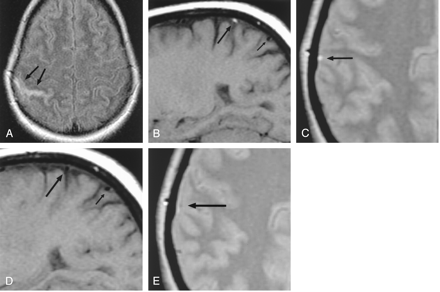

Patient 1, a 29-year-old woman with headaches, seizures, and cortical venous thrombosis.

A, Axial FLAIR (10,002/158/2200) [TR/TE/TI] MR image shows focal sulcal hyperintensity at the right frontoparietal convexity (arrows).

B, Right parasagittal T1-weighted (500/14) MR image shows tubular hyperintense thrombus (arrows) in a right convexity cortical vein, probably the vein of Trolard.

C, Right parasagittal T1-weighted (500/14) MR image, obtained approximately 3 months after the FLAIR image in panel A, shows resolution of the hyperintense thrombus (arrows).

D and E, Source data from MR venograms obtained at presentation (D) and approximately 3 months later (E) show interval appearance of flow signal intensity (arrows) in the previously occluded cortical vein.

Heparin and warfarin anticoagulation were initiated. She was also maintained on dilantin for seizure prophylaxis. A comprehensive hypercoagulability workup was unrevealing. The patient improved and continued to take warfarin as an outpatient.

Follow-up MR imaging was obtained approximately 3 months after the patient’s initial presentation. This examination showed interval resolution of the clot in the cortical vein (Fig 1C). In addition, partial recanalization of the thrombosed cortical vein was noted on MR venography (Figs 1D and E).